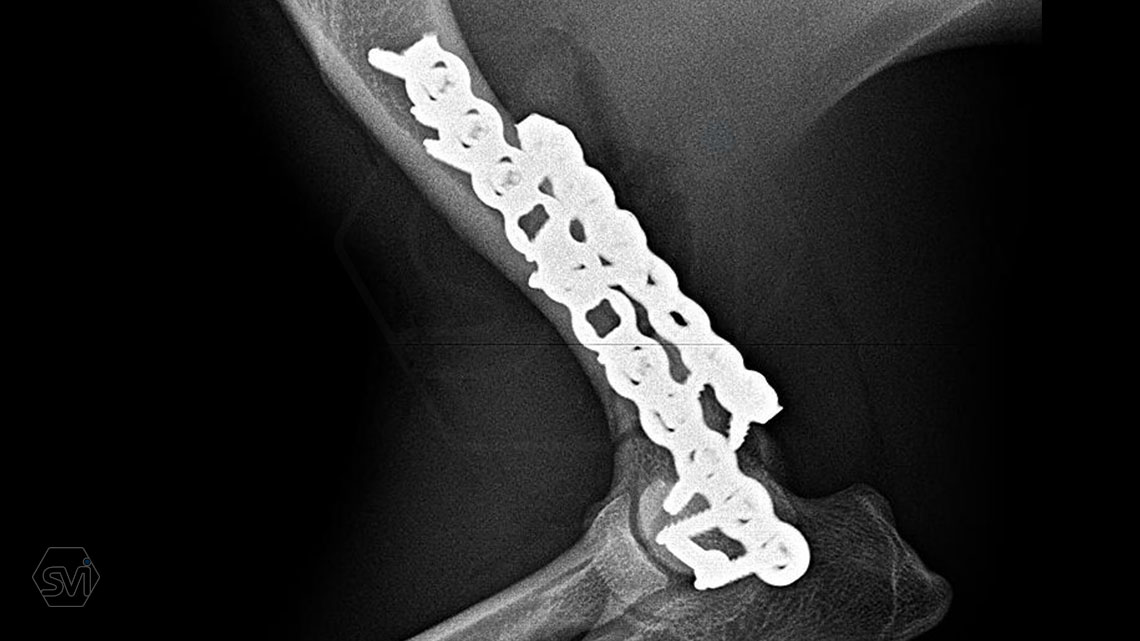

What used to be a nightmare type of surgery is slowly becoming my favorite: the humerus distal Y fracture